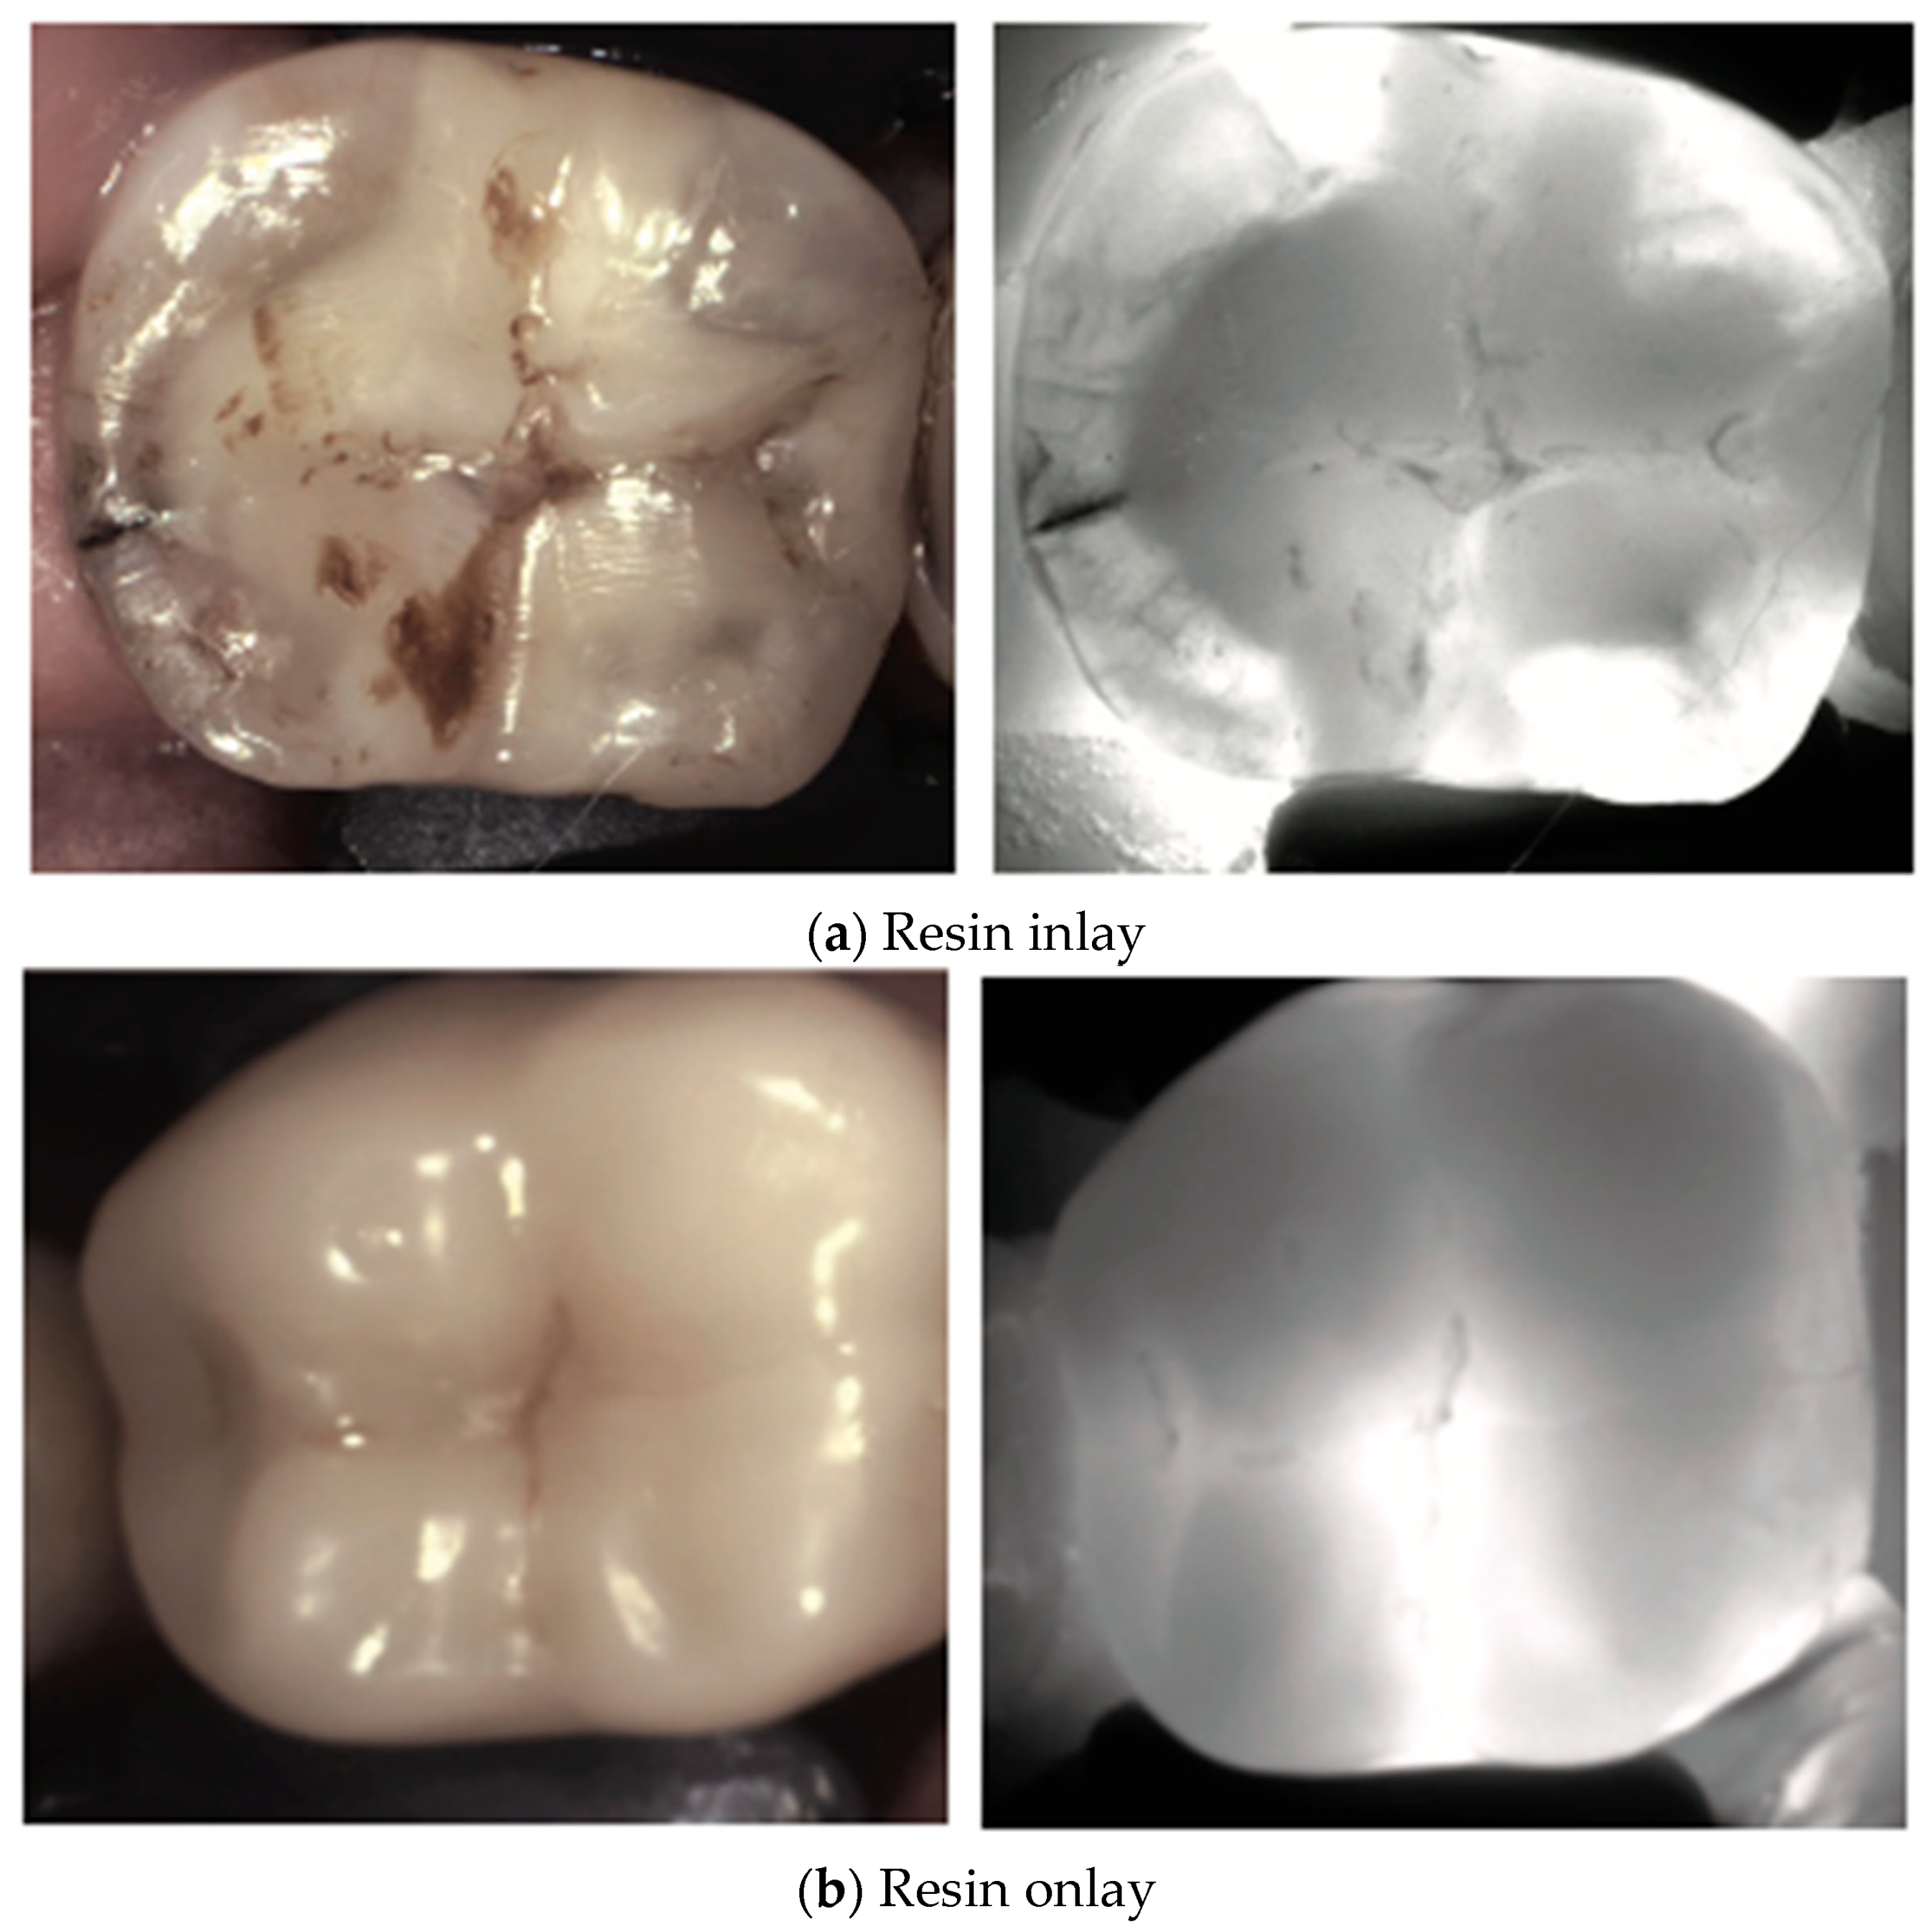

2. Carious Teeth

3. Restored Teeth